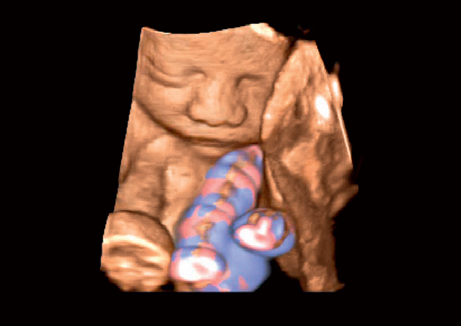

• 3D Color - цветное 3-х мерное изображение

• STIC Color - цветная объёмная визуализация сердца плода

• Трехмерная эхография в реальном времени с использованием специализированных 4D датчиков;

• Программа анализа сердца плода в трех проекциях в реальном времени 4D Stick;